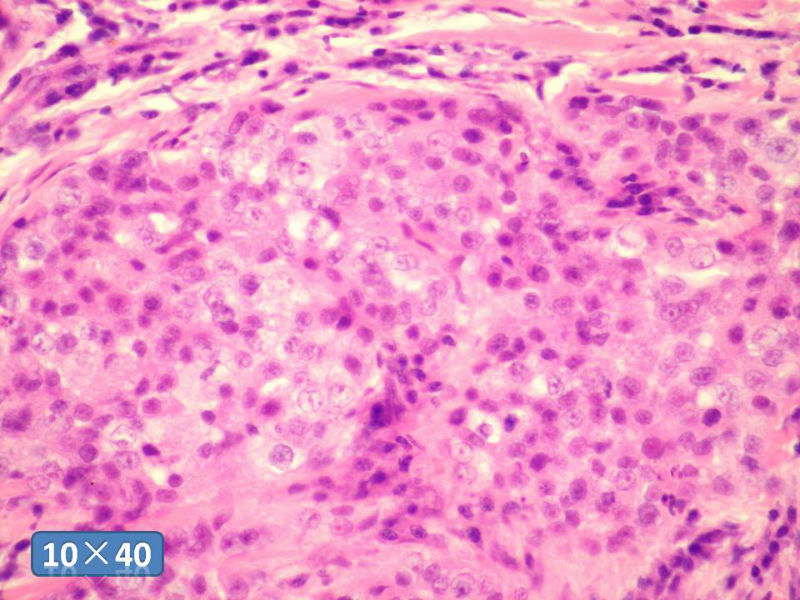

女性,50岁,乳腺肿物,冰冻切片(图1-25)

HE

IDC